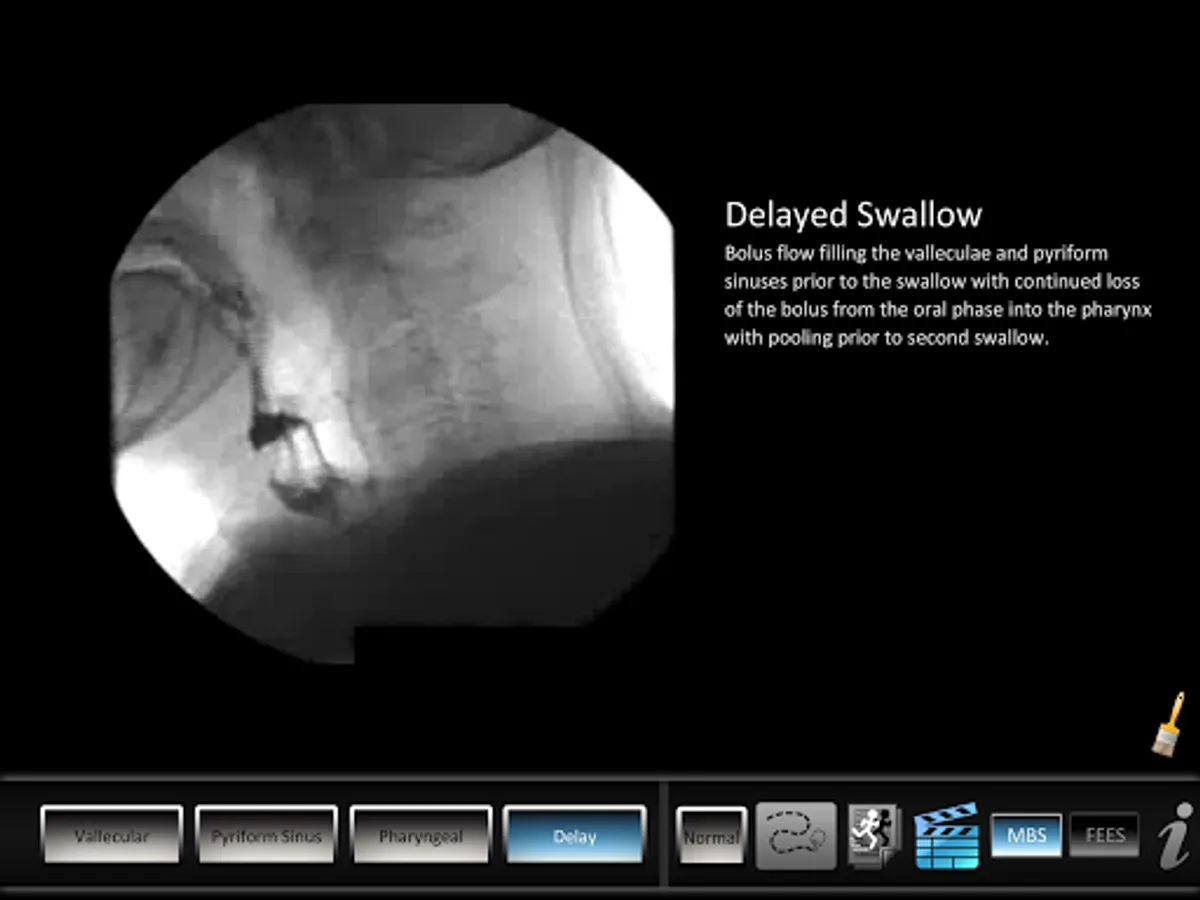

The Swallowing Residue app helps students and patients learn and professionals teach residue swallowing disorders. The app features normal, vallecular, pyriform, pharyngeal and delay views. Animated anatomical illustrations, key disorder highlight and a video for each view help patients and students learn.

• Key disorder highlight, animation and video for each vallecular, pyriform, pharyngeal and delay views.

• MBS and FEES video for each disorder.